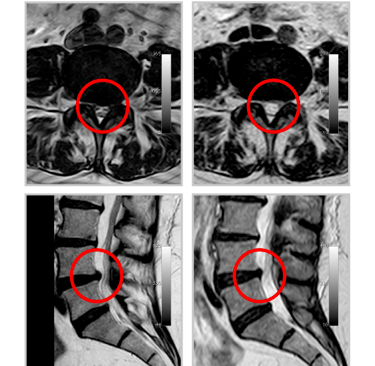

Insérer l’aiguille d’accès sous contrôle scanner dans le disque. (Vérifier le mode d'accès le plus approprié en fonction de la procédure cervicale ou thoracolombaire)